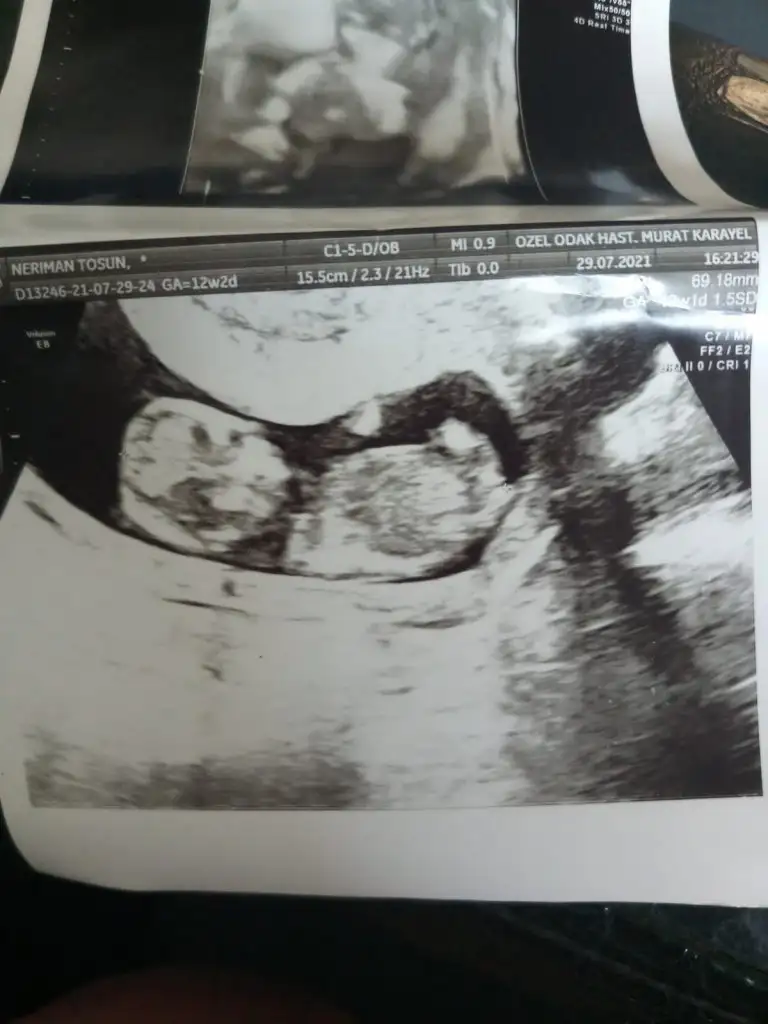

Erkek gibi sanki emin olamadım en iyi 11 12 13 haftalarEki Görüntüle 2896935 merhabalar tahmininizi alabilir miyim. SAT a göre 13+1 usg de 14 çıktı

Benimkine bakabildiniz mi acabaIkra meyra merhabalar, 12+2 haftalık görüntü. Tahminde bulunabilir misin?